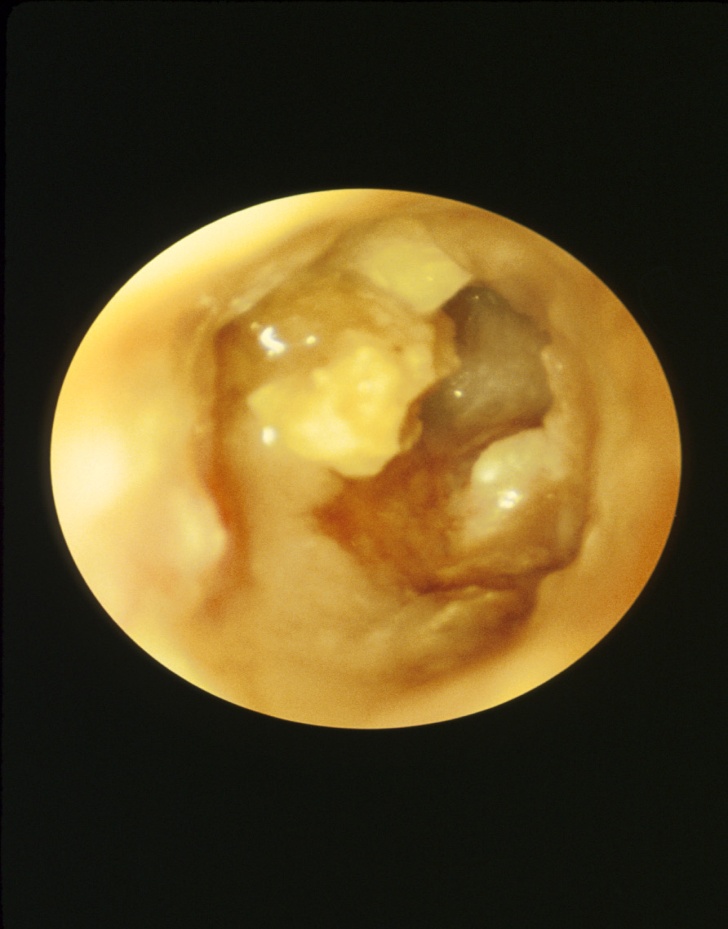

膽脂瘤容易受細菌感染引致病者經常性耳朵流膿(如圖二所示),更會擴展並破壞耳膜和耳骨,引致傳導性耳聾(conductive deaf)。膽脂瘤更可侵入內耳引致眩暈和面神經癱瘓。如果細菌感染沒有及時治理,細菌可以擴散入腦引致腦膜炎和腦膿腫,甚至可致死亡。

耳鏡檢查可診斷(如圖二所示)後天性膽脂瘤。電腦掃瞄可檢查膽脂瘤的擴散範圍,純音聽力圖(pure tone audiogram)則檢查耳膜和耳骨引致傳導性耳聾的程度。

■圖二